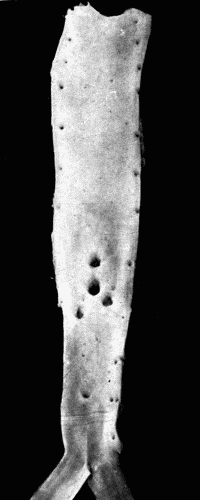

Fig. 3.—Arteriosclerosis of the thoracic and abdominal aorta, showing irregular nodules, atheromatous plaques, denudation of the intima, thin plates of bone scattered throughout with spicules extending into the lumen of the vessel. Note the contraction of the openings of the large branches, the rough appearance of the aorta and the greater degree of sclerosis of the upper two-thirds, i. e., of the aorta above the diaphragm. This aorta in the recent state was much thickened and almost inelastic. Fig. 3.—Arteriosclerosis of the thoracic and abdominal aorta, showing irregular nodules, atheromatous plaques, denudation of the intima, thin plates of bone scattered throughout with spicules extending into the lumen of the vessel. Note the contraction of the openings of the large branches, the rough appearance of the aorta and the greater degree of sclerosis of the upper two-thirds, i. e., of the aorta above the diaphragm. This aorta in the recent state was much thickened and almost inelastic.